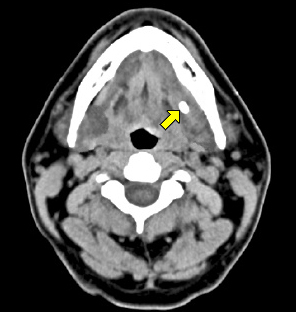

식후 동통 및 종창(부어오름)의 증상을 호소하는 경우, 우선 시진과 촉진을 시행한다. 턱밑샘 타석은 침샘관이 지나가는 구강저(혀와 잇몸 사이 부분)를 양손으로 촉진하면 만져진다. 반면 타액선 내 타석은 촉진으로 진단하기 어렵고, 경부 컴퓨터 단층촬영(목 부분의 CT)을 시행하여 뼈처럼 하얗게 보이는 타석이 있는지 관찰한다. 특히 귀밑샘 타석은 진단하기 매우 어려운데, 대부분 타석의 크기가 작고 촉진 상 뺨의 볼 조직에 묻혀 있으며 80%의 타석이 방사선 투과성을 가지기 때문이다. 이외에 구강 저 단순촬영, 타액선 조영술, 초음파 등도 진단에 이용될 수 있는 검사법이다. 1) 촉진: 한 손은 입 속에서, 다른 한 손은 목 밖에서, 손가락을 이용하여 침샘과 침샘관 부위를 만져보고 진단한다. 2) 경부 컴퓨터 단층촬영(CT): 침샘들을 중심으로 목 부위의 전산화 단층촬영(CT)을 시행하면 대부분 쉽게 타석증을 진단할 수 있어 일차 검사로 이용된다. 드물지만, CT에 나타나지 않는 타석도 있다. 3) 구강저 단순촬영: 턱밑샘의 타석을 진단하는 방법으로 단순 방사선촬영을 이용할 수 있는데, 최근에는 해부학적인 위치를 잘 관찰할 수 있는 CT 검사를 주로 이용한다. 4) 타액선관 조영술: 타액선관에 가느다란 관을 넣고 조영제를 주입하여 타액선관의 상태, 타석의 유무, 위치 등을 검사하는 방법이다. CT 검사에서 나타나지 않는 타석을 찾는 데 쓰일 수 있다. 5) 초음파 검사: 초음파는 타석을 투과하지 못하는 성질이 있으므로 침샘이나 침샘관 주위를 초음파로 관찰하면 타석을 진단할 수 있다.

타석증 CT